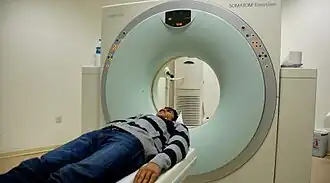

Computed tomography (CT) scanner, a commonly recommended screening technique | |

Results from large randomized studies have recently prompted a large number of professional organizations and governmental agencies in the U.S. to now recommend lung cancer screening in select populations. The 3 main types of lung cancer screening are low-dose, computerized tomographic (LDCT) screening, chest x-rays, and sputum cytology tests.[4] Currently multiple professional organizations, as well as the United States Preventive Services Task Force (USPSTF), the Centers for Medicare and Medicaid Services (CMS) and the European Commission's science advisors[5] concur and endorse low-dose, computerized tomographic screening for individuals at high-risk of lung cancer.